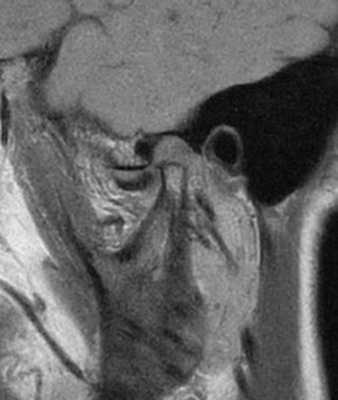

69-летняя пациентка с основными жалобами на боли в проекции челюсти, ограниченное открытие полости рта и невозможностью выдвинуть челюсть вперед обратилась за стоматологической помощью. Со слов пациентки ее симптомы начали развиваться около 6 месяцев назад: именно тогда она заметила, что ей трудно выдвигать челюсть вперед, чтобы посвистеть к своей собаки. По данным анамнеза на протяжении около 50 лет больная отмечала «выскакивание» и «пощелкивание» челюсти с левой стороны, и данные симптомы прекратились приблизительно в то время, когда ей стало трудно выдвигать нижнюю челюсть вперед. В ходе клинического осмотра было обнаружено, что максимальная величина межрезцового расстояния составляла 35 мм, при этом в ходе максимального открытия полости рта челюсть несколько смещалась влево. После массажа и растяжения левой жевательной мышцы и сустава снизилась интенсивность болевых ощущений, однако объем движений не увеличился. Таким образом был поставлен диагноз левостороннего смещения суставного диска без сопровождающейся редукции ВНЧС. Пациентка была направлена на магнитно-резонансную томографию (МРТ), и для исследования локализации и состояния диска при открытом и закрытом рте. Данные МРТ позволили установить, что с левой стороны отмечалось переднее смещение суставного диска в обеих положения, что также подтверждает диагноз смещения без редукции (фото 1-4).

Фото 3. МРТ-скан левого ВНЧС при закрытом состоянии рта: визуализация переднего смещения диска без редукции.

Фото 4. МРТ-скан левого ВНЧС при закрытом состоянии рта: визуализация переднего смещения диска без редукции.